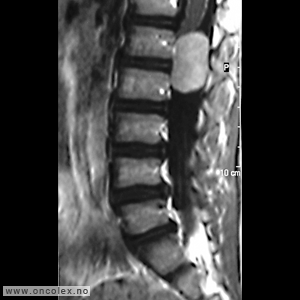

Bildediagnostiske undersøkelser

MR er det viktigste diagnostiske hjelpemiddel for å påvise svulst i ryggmargen, ryggmargsnervene og ryggmargshinnene. CT kan også brukes, men har klare begrensninger når det gjelder fremstilling av svulstene. Blant annet kan svulster som ikke tar opp kontrast bli oversett. CT og skjelettrøntgen kan imidlertid være nyttig for å kartlegge grad av skjelettødeleggelse og eventuell instabilitet i ryggsøylen.